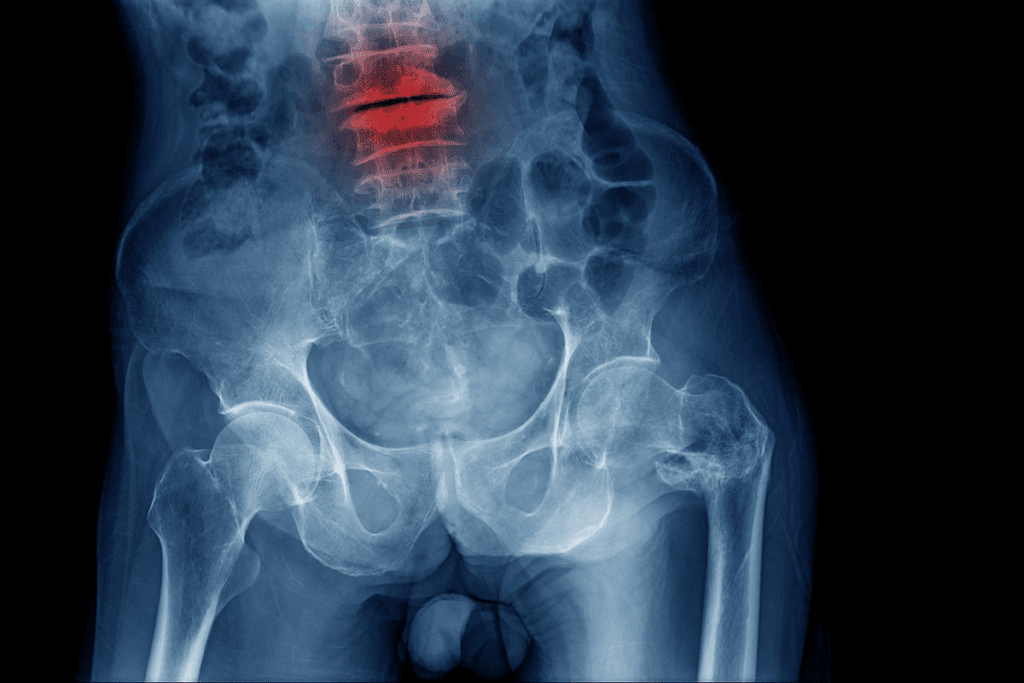

Lumbar (Lower Back) Facet Injections

Lumbar facet injections are common for lower back pain. They inject medication into the affected joints. This helps reduce inflammation and pain.

They’re used when other treatments don’t work. These injections can both find and treat the pain source.